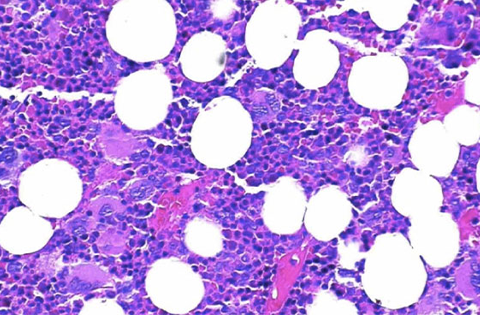

Anemia aplásica

Fallo de la médula ósea para producir células sanguíneas